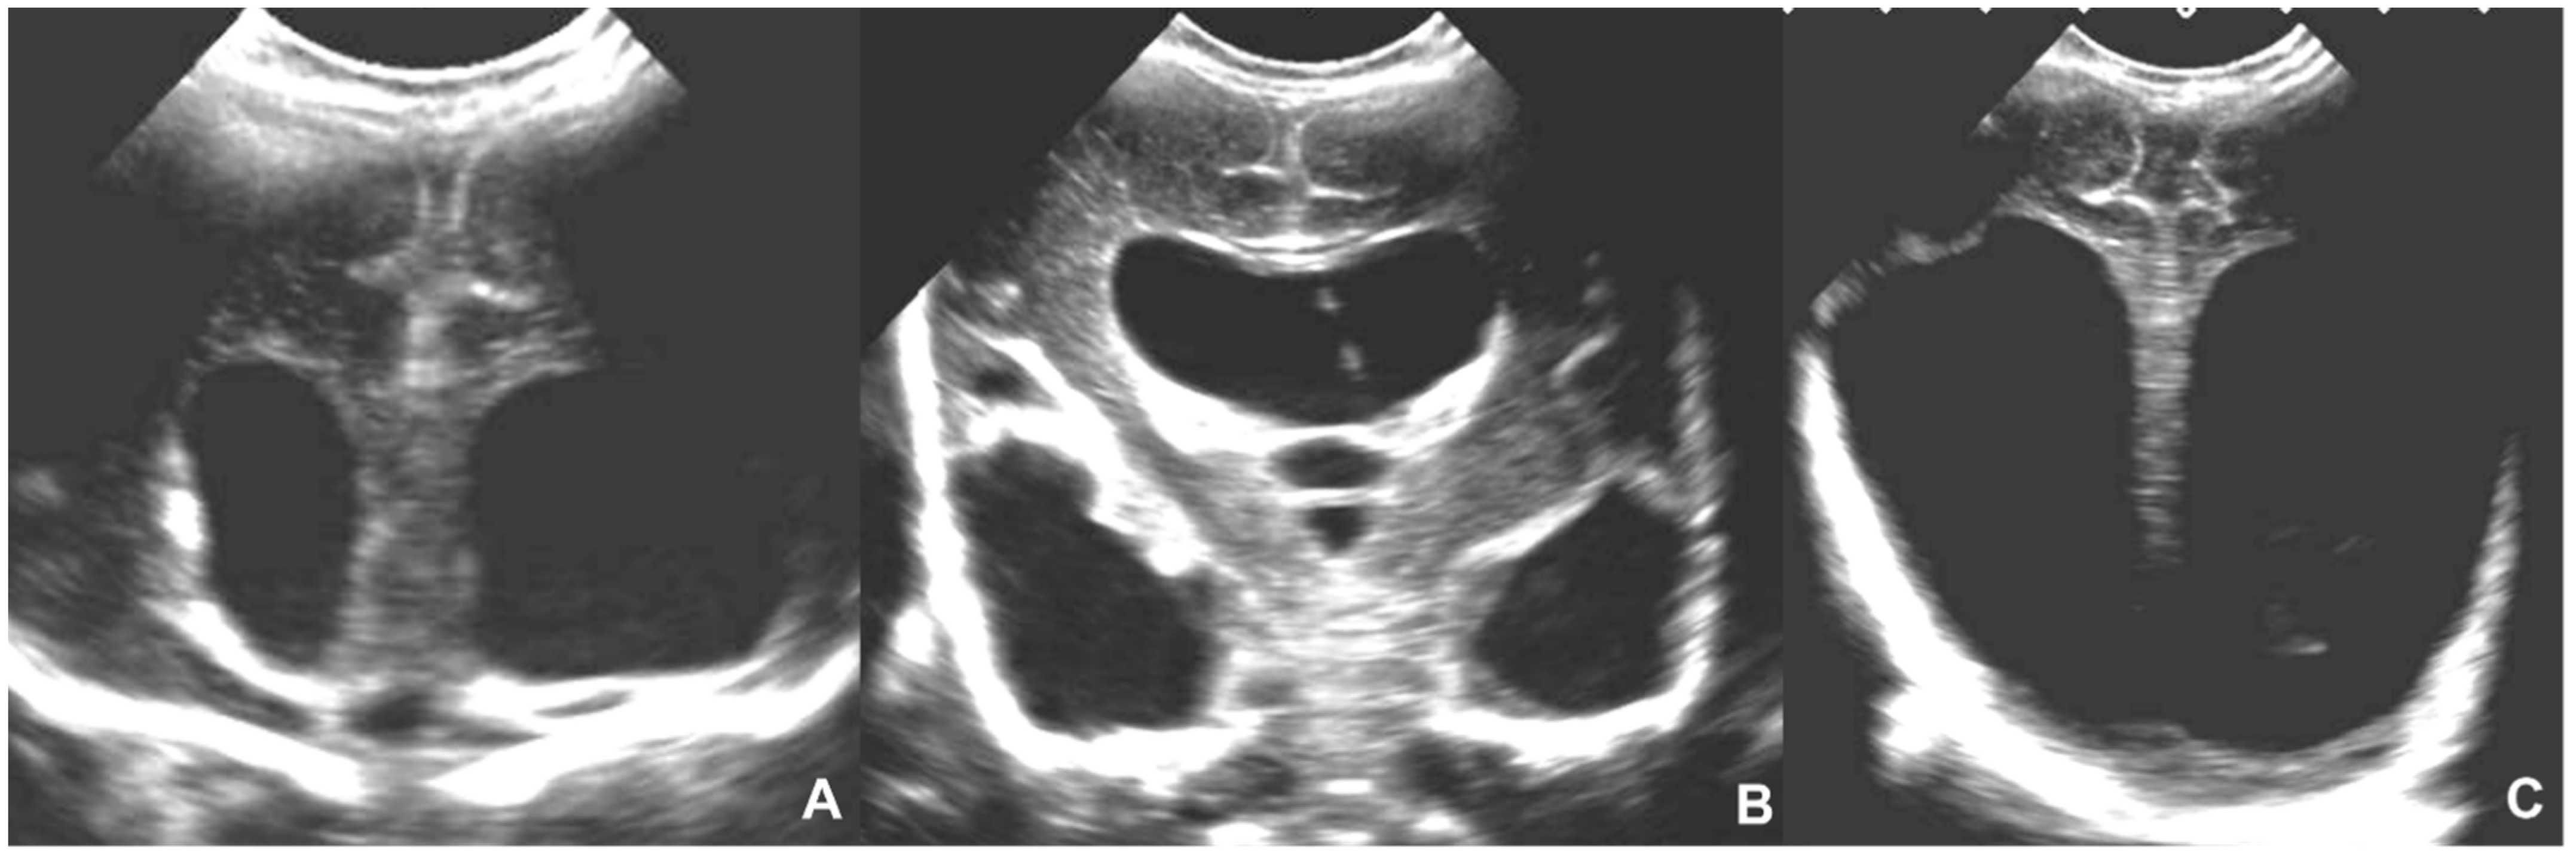

- Epelman, M.; Daneman, A.; Blaser, S.I.; Ortiz-Neira, C.; Konen, O.; Jarrín, J.; Navarro, O.M. Differential diagnosis of intracranial cystic lesions at head US: Correlation with CT and MR imaging. Radiographics 2006, 26, 173–196. [Google Scholar] [CrossRef]

- Beltinger, C.; Saule, H. Sonography of subependymal cysts in congenital rubella syndrome. Eur. J. Pediatr. 1988, 148, 206–207. [Google Scholar] [CrossRef]

- Yamashita, Y.; Matsuishi, T.; Murakami, Y.; Shoji, H.; Hashimoto, T.; Utsunomiya, H.; Araki, H. Neuroimaging findings (ultrasonography, CT, MRI) in 3 infants with congenital rubella syndrome. Pediatr. Radiol. 1991, 21, 547–549. [Google Scholar] [CrossRef]